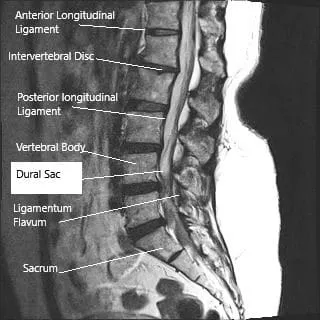

Sagittal section (MRI) of the lumbar spine showing dural sac.